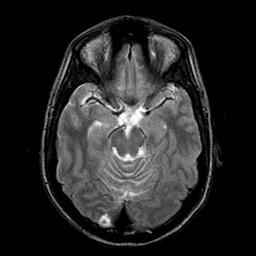

Sarcoma, MR Study #1 mr-t2 -- Slice #8

[Home][Help][Clinical] Slice 8